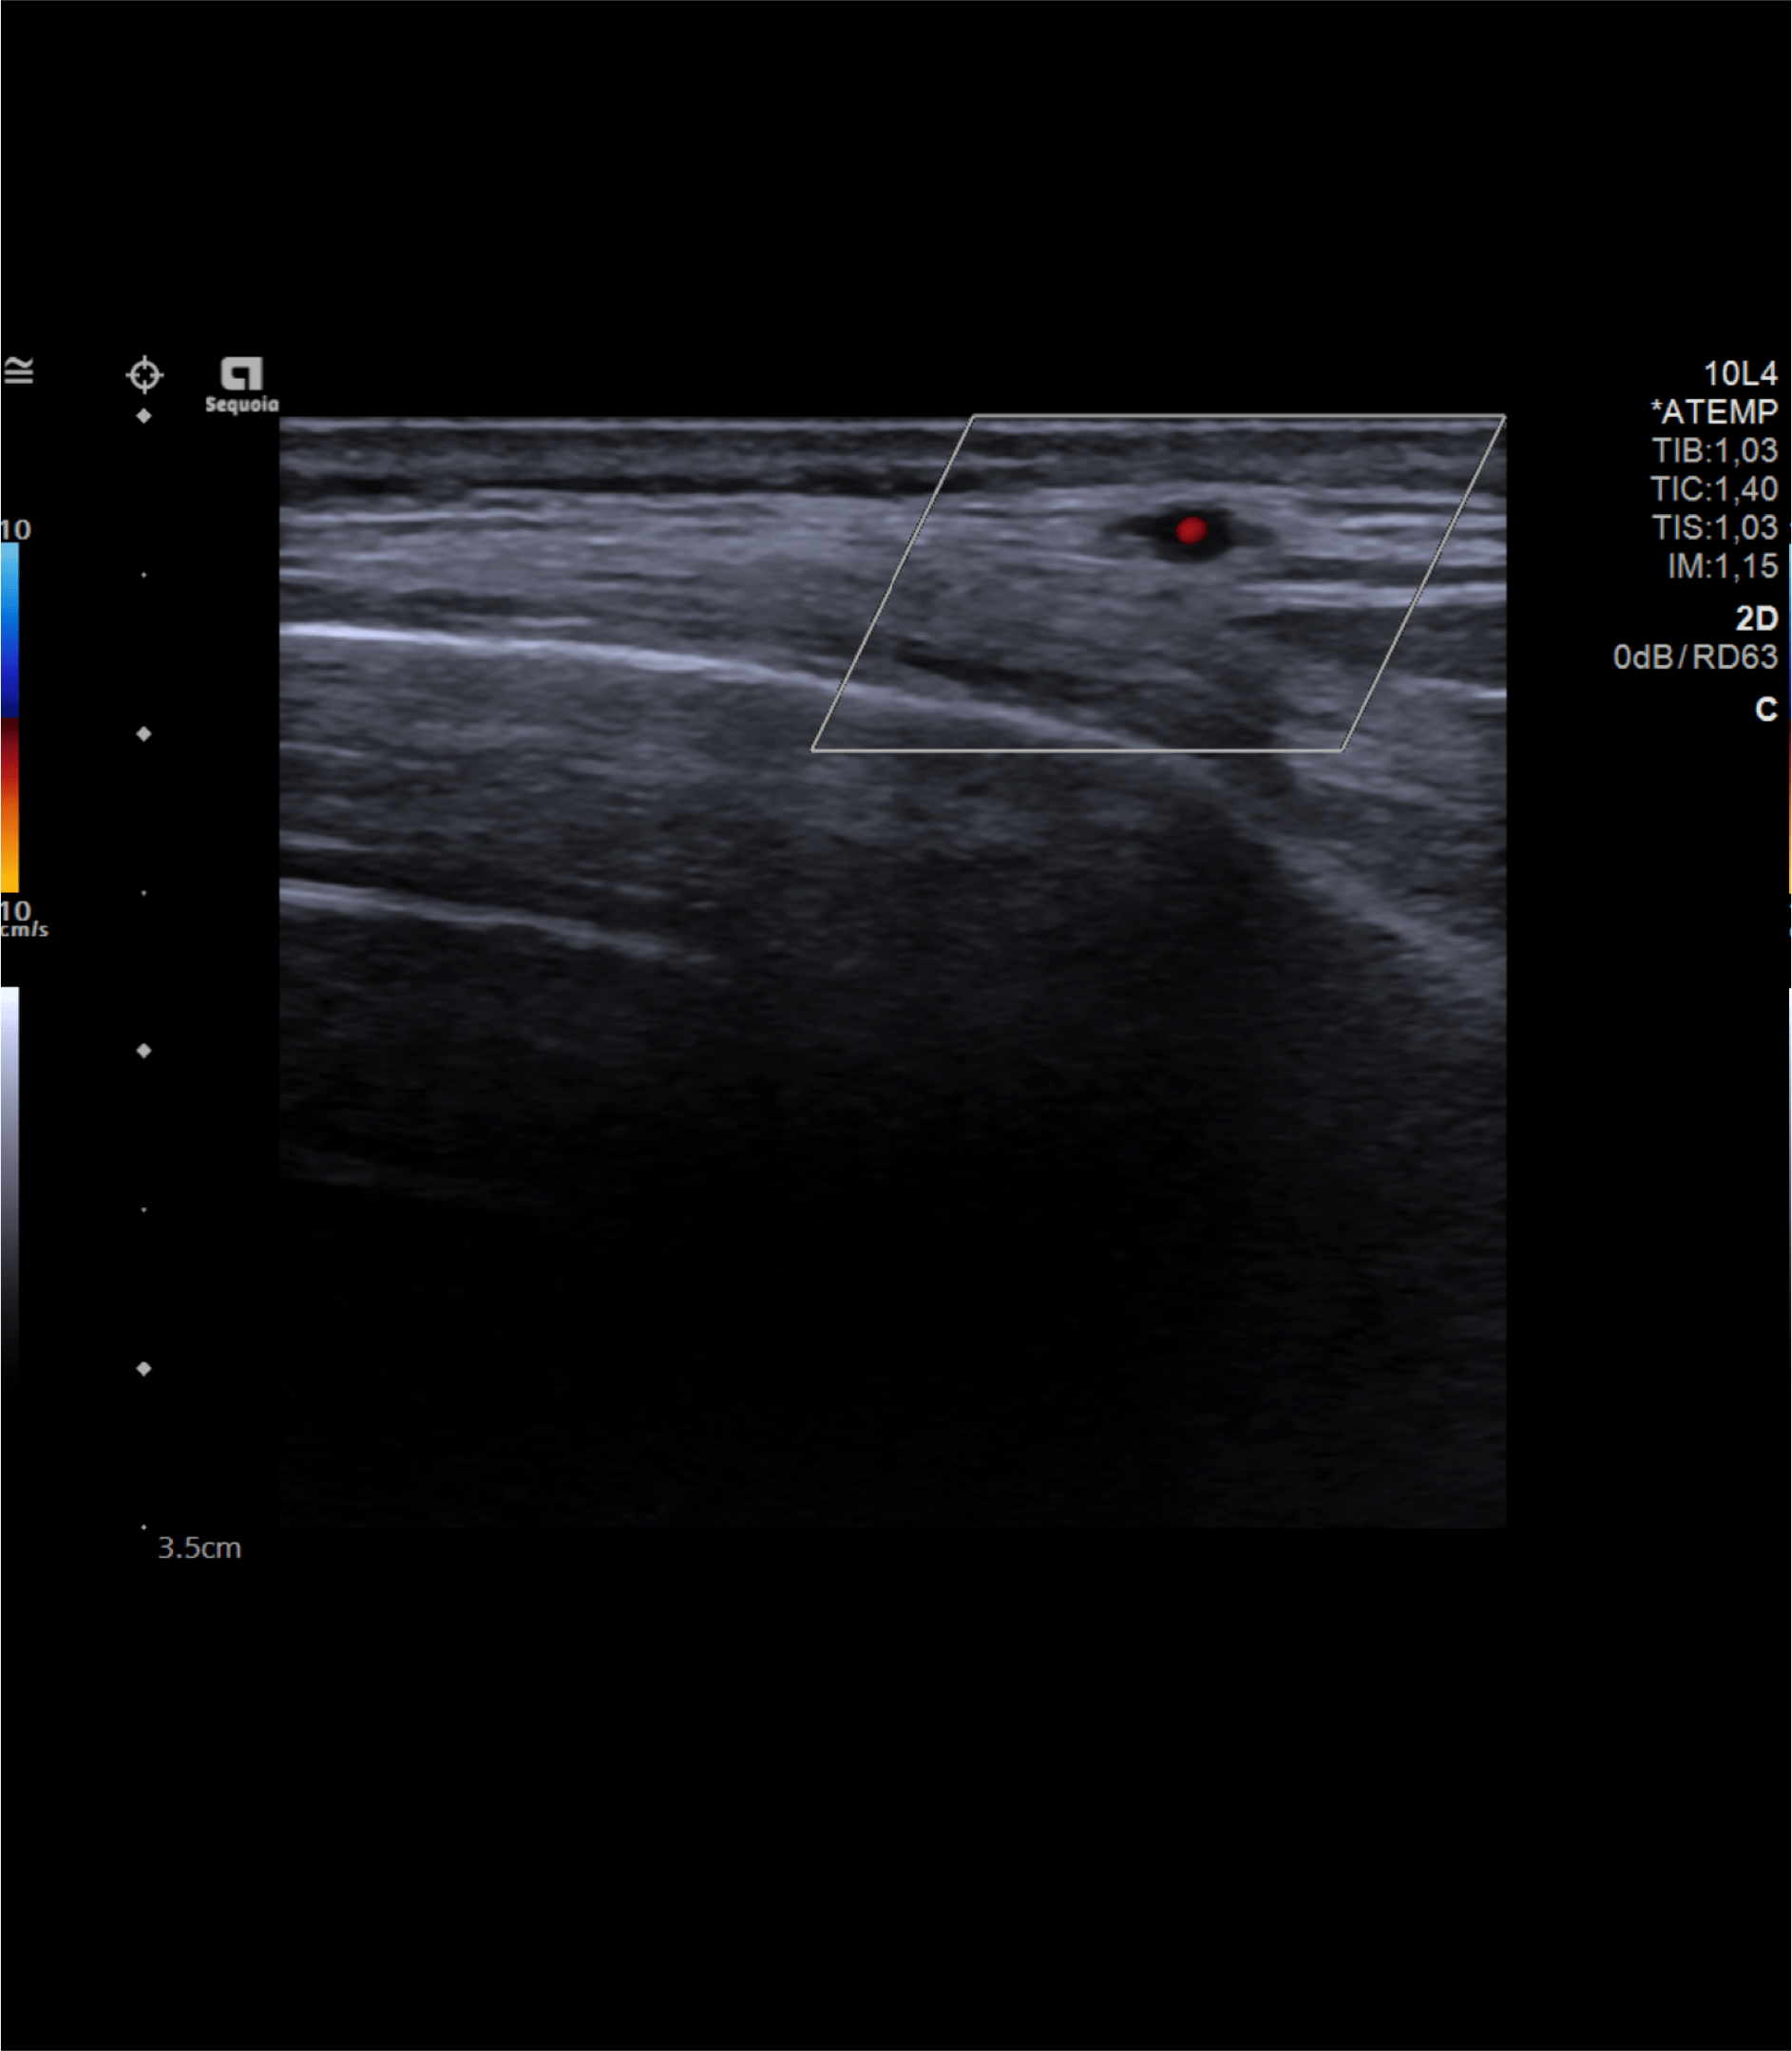

Realizamos una ecografía centrada en la zona temporal derecha del paciente.

Hallazgos ecográficos

Observamos engrosamiento parietal de arteria temporal iderecha con halo hipoecoico periférico, disminución de su calibre y cambios inflamatorios asociados.

El paciente ingresó a cargo de Neurología donde solicitaron ecografía modo Doppler de ambas arterias temporales y RMN cerebral. Además, fue valorado por Oftalmología.

En conclusión, ante un paciente de edad avanzada y síntomas que hagan sospechar la presencia de una arteritis de la temporal debe considerarse la realización de una ecografía modo Doppler para su diagnóstico y así evitar el retraso del diagnóstico definitivo mediante biopsia.